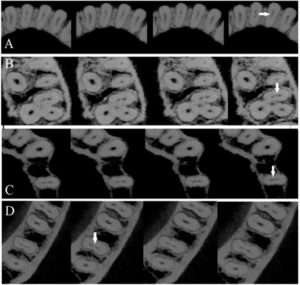

192 – Clasificación propuesta para los contactos interproximales de los molares primarios utilizando CBCT: Un estudio piloto

El «Área de contacto» es un término que se usa para denotar las alturas proximales del contorno de las superficies mesial y distal del diente.